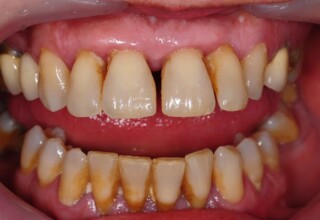

Αποκατάσταση διαστημάτων μεταξύ κεντρικών και πλαγίων τομέων

Τα διαστήματα έχουν δημιουργηθεί κυρίως λόγω των στενών πλαγίων. Μετά την ολοκλήρωση της ορθοδοντικής θεραπείας τα διαστήματα “έκλεισαν” με την τοποθέτηση δύο αποκαταστάσεων σύνθετης ρητίνης.